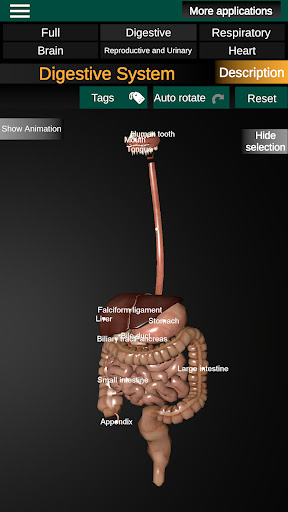

* Digestive system, including the stomach, small intestine, large intestine, and an animation of this system.